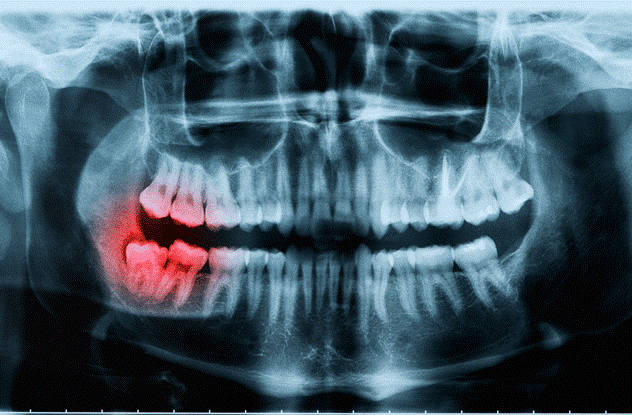

دندان های عقل در سنین 17 تا 25 سالگی به عنوان آخرین دندان در انتهای راست و چپ فک بالا و پایین می روید. در واقع هر فردی باید شاهد رویش 4 دندان اضافه تحت عنوان دندان عقل در دهانش باشد. در برخی افراد اگر دندان عقل نتواند مسیر رشد خود را پیدا کند و از لثه بیرون آید، در همان جا به صورت نهفته باقی می ماند و سبب آسیب رساندن به دندان های دیگر می شود. این دندان ها به طور کامل رشد نمی کنند، به همین دلیل می گوییم این گونه افراد دندان عقل نهفته دارند. اگر نسبت به تشخیص دندانپزشک لازم شد دندان های عقل تان کشیده شود، باید حتماً سعی کنید تا دیر نشده و در سن پایین تر این کار را انجام دهید. هرچه از زمان رشد دندان عقل بگذرد ریشه محکم تر به لثه و فک می چسبد. در این صورت کشیدن دندان بسیار دشوار و دردناک می شود.

در برخی افراد به دلیل کوچک بودن فک و عدم وجود فضای کافی برای رشد دندان ها، دندان عقل به صورت طبیعی ( بهصورت عمودی ) رشد نمی کند و رشد خود را به صورت افقی ادامه می دهد. در این جا فرد با مشکلاتی از قبیل جا به جا شدن دندان های دائمی و کج شدن آن ها رو به رو می شود. برخی افراد نیز با فشاری که ریشه دندان های عقل به دیگر دندان ها وارد می کنند با درد و ناراحتی دست و پنجه نرم می کنند. برخی افراد نیز هنگام جویدن غذا و دیگر خوراکی ها درد زیادی را در ناحیه دندان عقل متحمل می شوند، اما خوشبختانه اکثر افراد با رویش دندان های عقل خود مشکلی ندارند. جالب است بدانید رشد افقی دندان علاوه بر سمت راست و چپ فک می تواند به سمت پشت دهان نیز ادامه یابد.

اگر دندان عقل موجب آزار شما شده است، میتوانید با مشورت دندانپزشک و بررسی های لازم آن را بکشید. دندانپزشک معالج از شما می خواهد تا عکس های واضحی از فک بالا و پایین بگیرید تا تشخیص روند کشیدن و زمان کشیدن برای دندانپزشک راحت تر شود. اگر دندان عقل حالت عادی داشته باشد و مانند سایر دندان ها در جای خود ماندگار باشد احتیاجی به کشیدن آن نیست، اما اگر مشکلاتی از قبیل درد، حساسیت، تأثیرگذاری بر دیگر دندان ها و… را دارد بهتر است نزد دندانپزشک حرفه ای بروید و مشکل را با وی در میان بگذارد.

اگر به نظر داندانپزشک معالج دندان عقل شما باید حتماً کشیده شود، نکته ی بعدی که بسیار حائز اهمیت می باشد بهترین زمان کشیدن دندان است. هر فردی نسبت به رشد دندانش و طریقه ی روییدن آن زمان کشیدنش نیز متفاوت می باشد. شدت درد در ناحیه ی فک ها، شدت علائم غیرطبیعی و جایگاه دندان می تواند در تنظیم زمان کشیدن دندان توسط دندانپزشک تأثیرگذار باشد. بهتر است بدانید دندان های عقل در فک پایین از اهمیت بیشتری نسبت به فک بالا برخوردارند. دلیل این امر وجود عصب در فک پایین می باشد.

در فک بالا هیچگونه عصبی وجود ندارد ازاین رو می توانید در صورت نیاز بدون هیچ گونه حساسیت و وسواسی دندان عقل موجود در فک بالا را بکشید. اما کشیدن دندان عقل در فک پایین به همین سادگی ها نیست. باید حتماً عکس رادیوگرافی گرفته شود. درصورتی که دندان در بین عصب وجود داشته باشد ریسک کشیدن دندان بسیار بالاست و حتی ممکن است منجر به کج شدن دائمی فک شود.